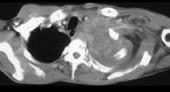

问题 男,68岁,咳嗽,胸痛,呼吸困难伴四肢无力半月余,请结合影像学检查,选出最可能的诊断 ( )

选项 A.肺癌 B.肺结核 C.淋巴瘤 D.纵隔畸胎瘤 E.恶性胸腺瘤

答案 E